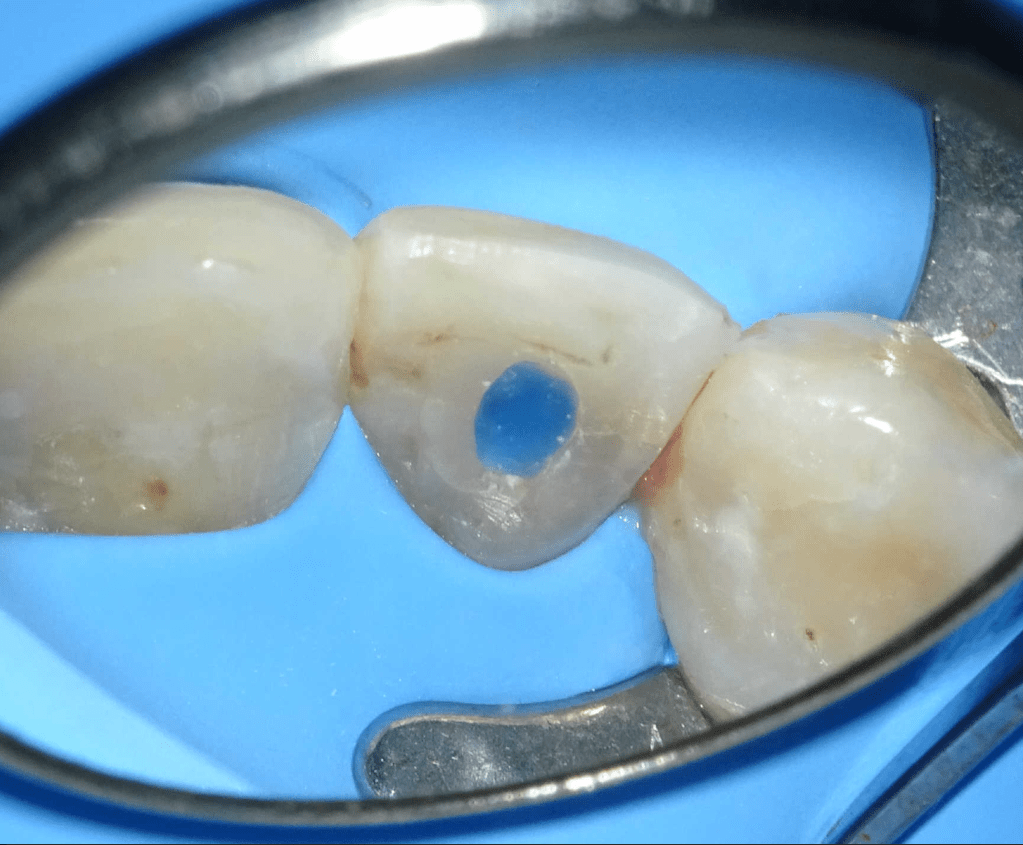

Pulpotomía biodentine + reco preendio